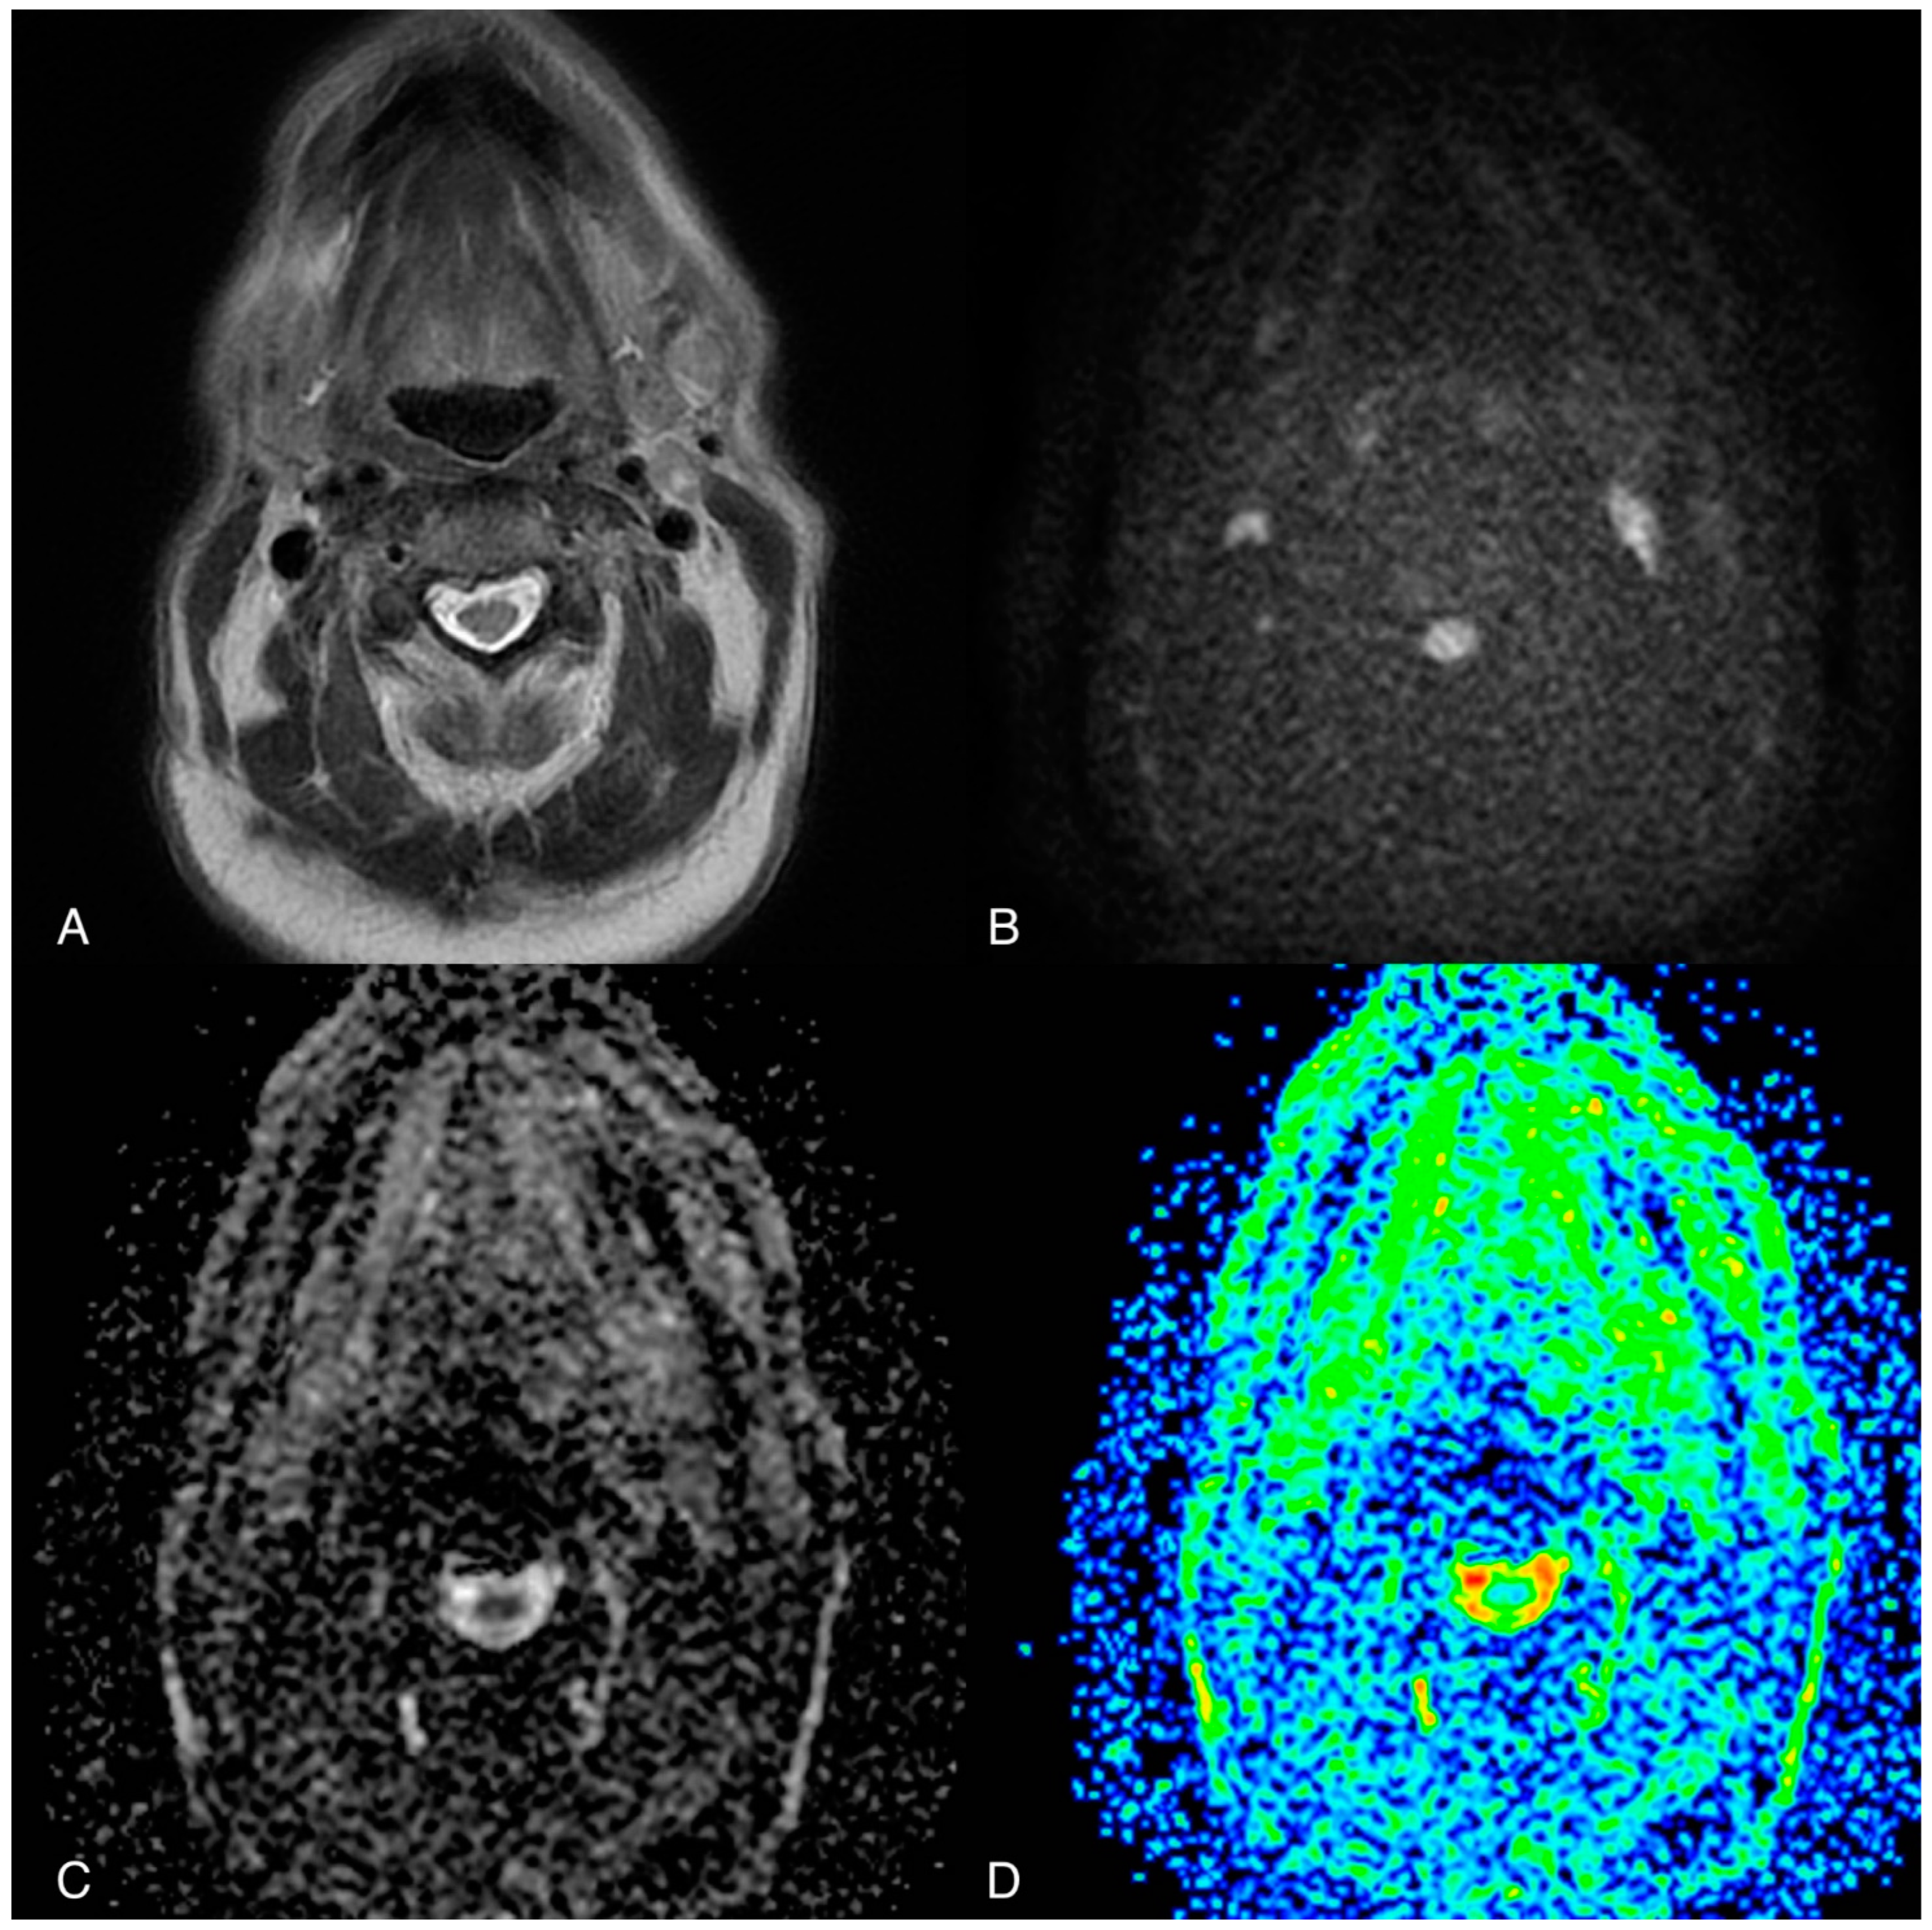

- Jović, A.; Fila, J.; Gršić, K.; Ivkić, M.; Ozretić, D. Diffusion-weighted MRI: Impact of the size of the ROI in detecting metastases in subcentimeter lymph nodes in head and neck squamous cell carcinoma. Neuroradiology 2020, 62, 987–994. [Google Scholar] [CrossRef] [PubMed]